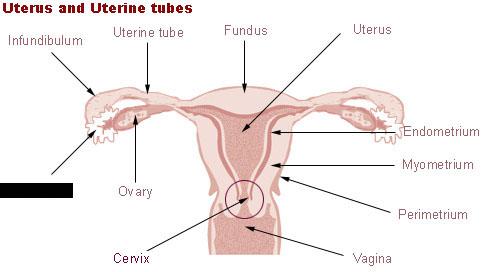

Cervix

Endometrium

Myometrium

Ovary

Perimetrium

Round ligament (of uterus)

Uterine (=fallopian) tube

Uterus

Vagina